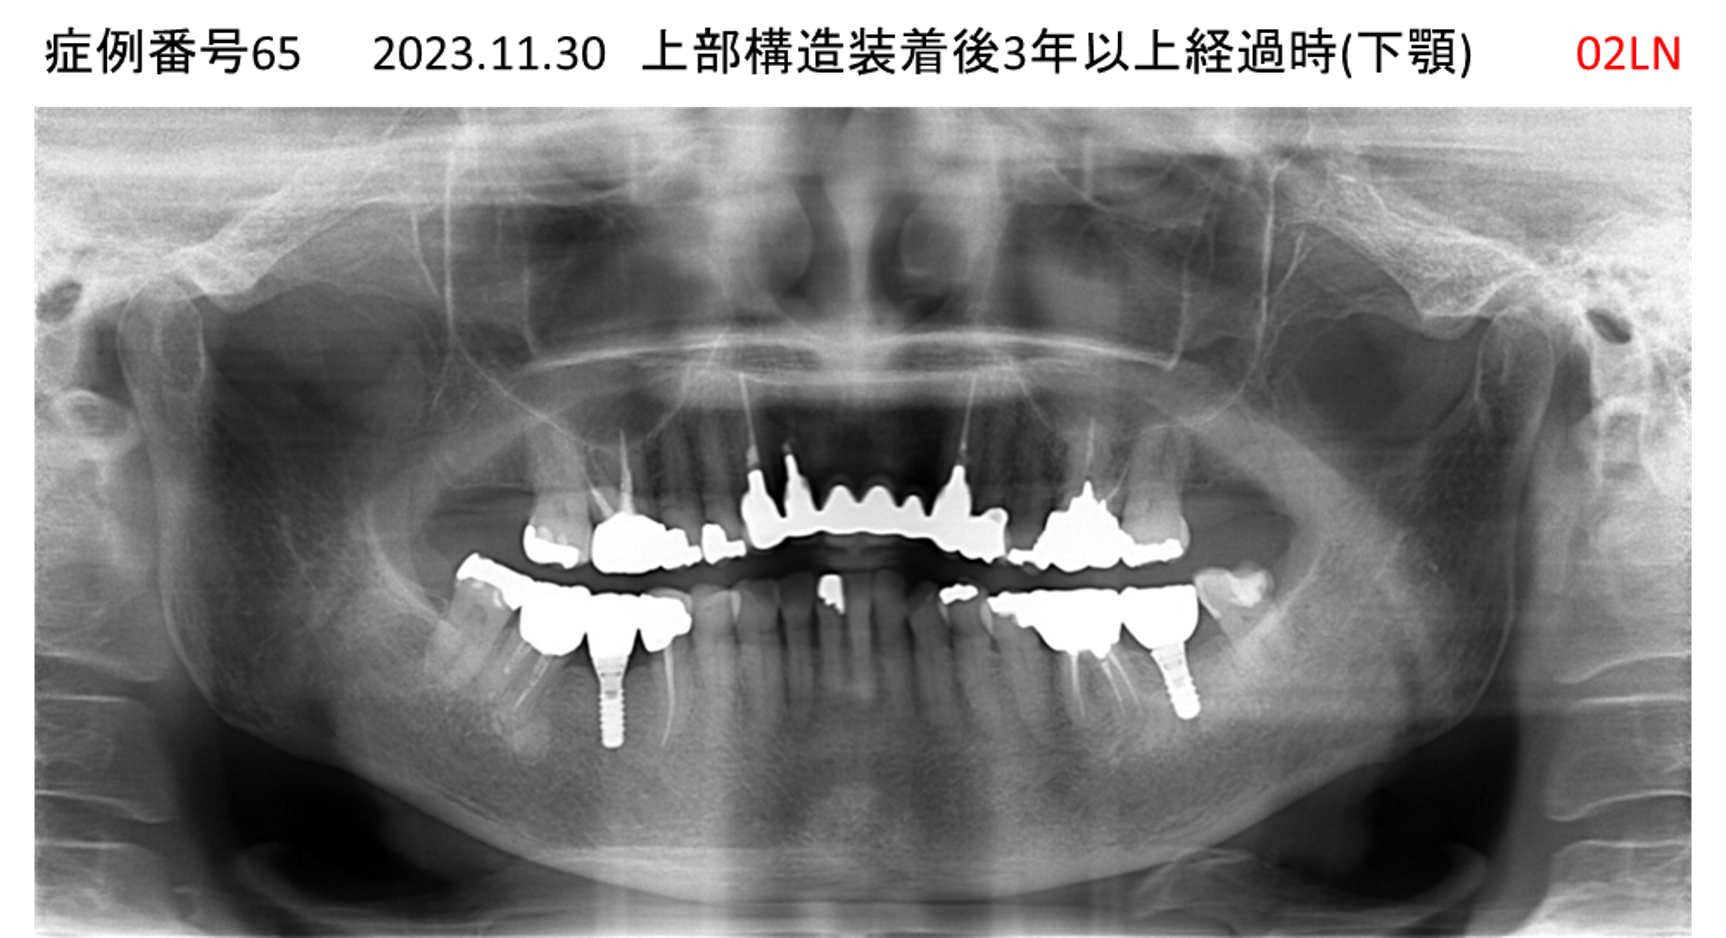

食事ができない/噛めない患者様のインプラント症例

| 治療名称 |

インプラント |

| 治療費用 |

540万円+税 |

| 治療期間 |

6か月 |

| 患者さんの症状(主訴) |

食事ができない。噛めない。上の前歯が揺れてきた。入れ歯がつらい。 |

| 治療内容 |

サイナスリフト、インプラント |

| 治療結果 |

なんでも食べられるようになった。力が入る(全身)ようになった。 |

| 治療の注意点(リスク/副作用) |

インプラントが壊れたら再治療が必要 |